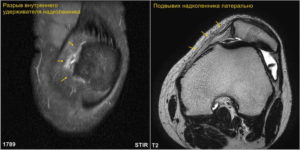

Анатомически надколенник имеет тенденцию к смещению кнаружи при движениях коленного сустава. Чем выше усилие, направленное на сгибание или разгибание, коленного сустава, тем сильнее надколенник смещается кнаружи. Этому смещению противостоят две анатомические структуры: блок бедренной кости и медиальнный (внутренний) удерживатель надколенника.

Если сила смещающая надколенник кнаружи превосходит упругость медиального (внутреннего) удерживателя, происходит разрыв этого удерживателя с вывихом надколенника, что сопровождается острой болью, ощущением того, что в коленном суставе «что-то сместилось и встало на место» и увеличением отека.